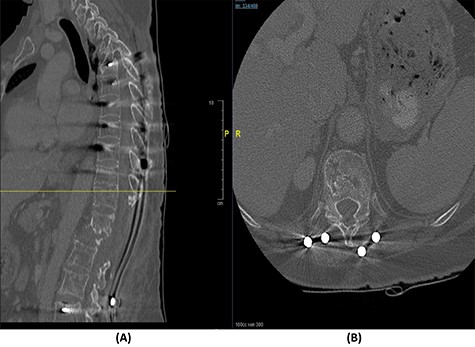

(A) Sagittal spine CT demonstrating a burst fracture involving L1 vertebral body with retropulsion of fragments and epidural soft tissue mass indenting the conus medullaris at the level of T12–L1. (B) Axial spine CT of the corresponding level of L2 vertebral body. (C) Axial spine CT of the corresponding level of L3 vertebral body. (D) Axial spine CT of the corresponding level of T11 vertebral body.

The bridging technique was used to achieve relative stability through posterior fixation until the anti-TB medications cleared the vertebral infection and allowed re-ossification of the destructed levels (T11–L3) to occur. An open biopsy was done intraoperatively to reconfirm the diagnosis of spinal TB. The patient started mobilizing early postoperatively and continued to take the anti-TB medications for 18 months (Fig. 4).